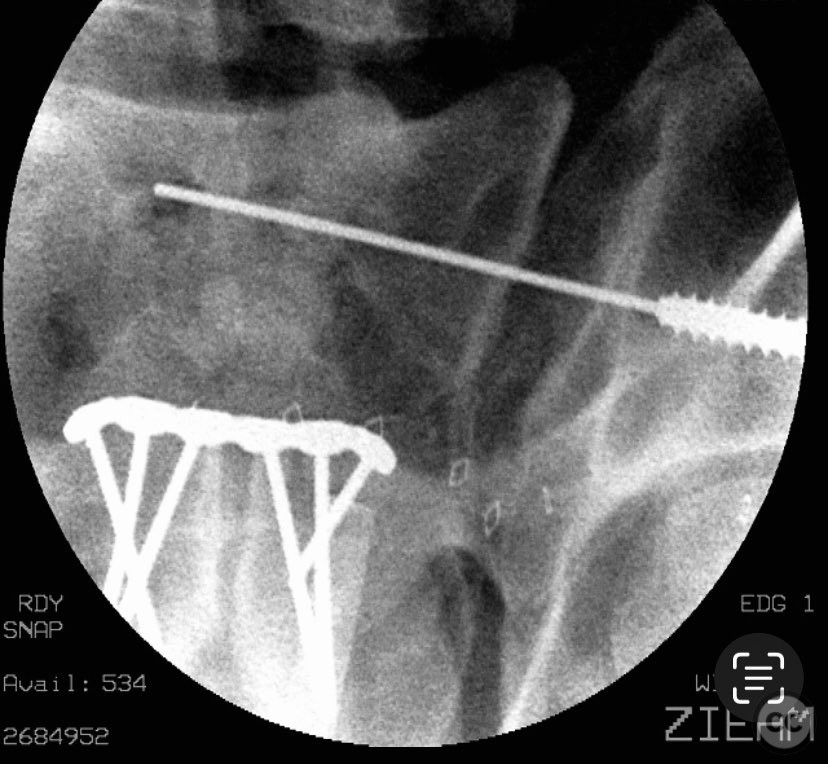

Anatomical surgical approach:  A lower midline infraumbilical incision was made to expose the symphysis pubis. Subperiosteal dissection was performed to mobilize the rectus abdominis insertions and expose the pubic bodies. A pelvic reduction clamp was applied with tines docked in dense bone or soft tissue as dictated by local tissue quality, oriented to correct deformity while avoiding interference with planned plate placement. Following reduction, a contoured anterior symphyseal plate was applied and secured with cortical screws. Upon removal of the clamp, persistent SI joint malreduction was noted. Under fluoroscopic guidance, a percutaneous pathway was prepared for a cannulated iliosacral lag screw, traversing the posterior ilium into the upper sacral segment, ensuring safe passage relative to neurovascular structures.

The intraoperative course revealed that indirect reduction of the incomplete SI joint injury via anterior stabilization was insufficient, necessitating direct percutaneous fixation. A single cannulated iliosacral oblique lag screw was inserted under fluoroscopic control, achieving reduction, compression, and stabilization of the SI joint. Surgeon-specific technical consideration included avoidance of large-diameter drills for the posterior ilium due to limited bone stock (approximately 3 cm of ilium available for purchase), and the preference for an appropriately sized washer to optimize compression without risking iatrogenic fracture.

Orthopaedic implants used:   3.5 mm anterior symphyseal plate with cortical screws; 7.0 mm cannulated iliosacral lag screw with washer